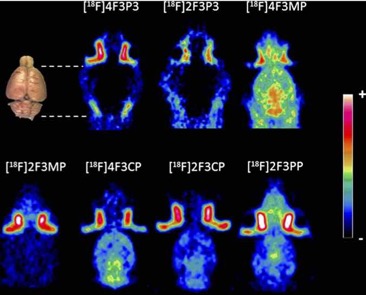

β Preclinical validation of [18F]2FNQ1P as a specific PET radiotracer of 5-HT6 receptors in rat, pig, non-human primate and human brain tissue

S. Emery, S. Fieux, B. Vidal, P. Courault, S. Bouvard, C. Tourvieille, T. Iecker, T. Billard, L. Zimmer, S. Lancelot

Nucl. Med. Biol. 2020, 82-83, 57-63.